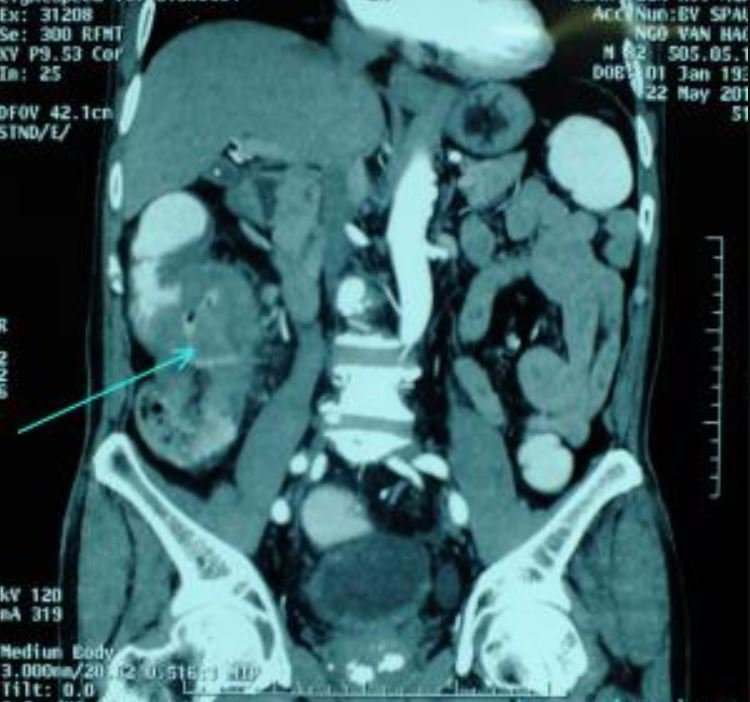

Ngoài nội soi sinh thiết xác định chẩn đoán, bệnh nhân được chụp cắt lớp vi tính đa dãy để đánh giá trước mổ